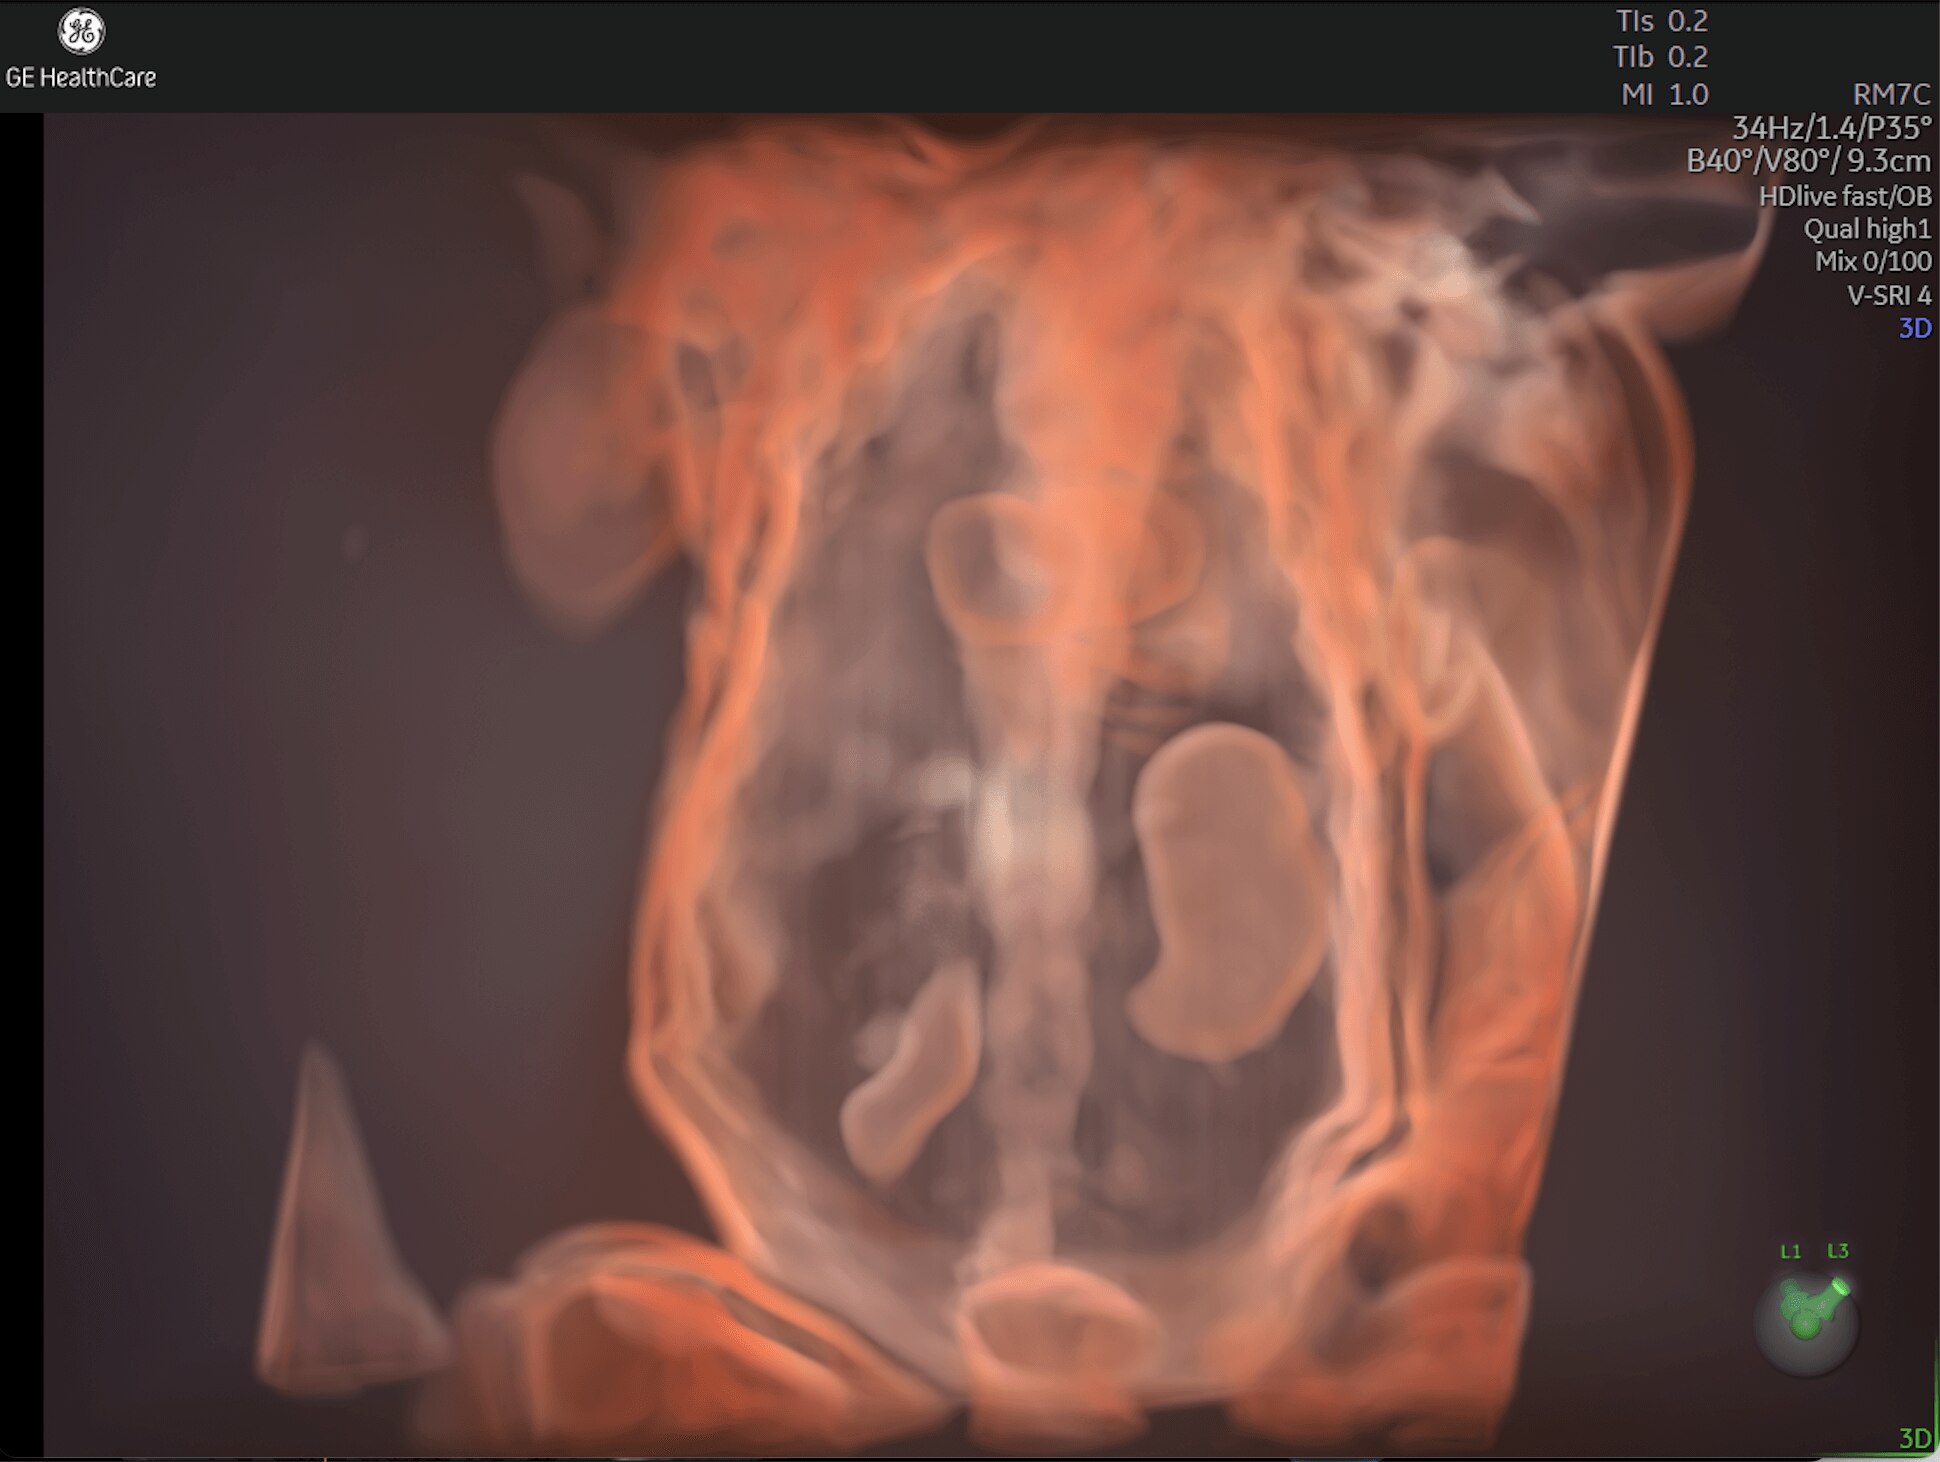

Enhanced Volume Imaging

Deliver next generation 3D/4D & Color images with HDlive Studio+

Unique Probe Technology

Obtain high resolution images with advanced probe technology - e M6C, RIC6-12, and RM7C